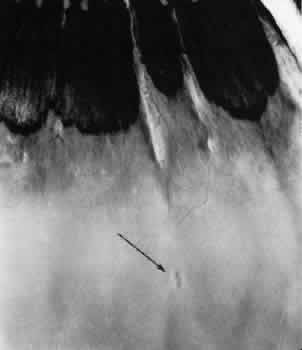

Fig. 12. Enclosed ora bay in a 35-year-old man. Anteriorly, two broad dentate processes converge and join to enclose a bay (island of pars plana). Posteriorly there is a focus of retinal thinning (peripheral retinal excavation; arrow). (× 12.)

PERIPHERAL RETINAL EXCAVATION

Peripheral retinal excavation appears as a rather small oval depression in the retina. Usually this lesion is aligned meridionally with a meridional fold or complex and located 1 to 7.2 mm posterior to the ora serrata (Fig. 13; see Figs. 6 and 12). The focal depression may be surrounded by margins that appear to be elevated; however, microscopic examination reveals that the depression corresponds to afocal loss of the inner retinal layers and that the surrounding tissue is normal (Fig. 14).